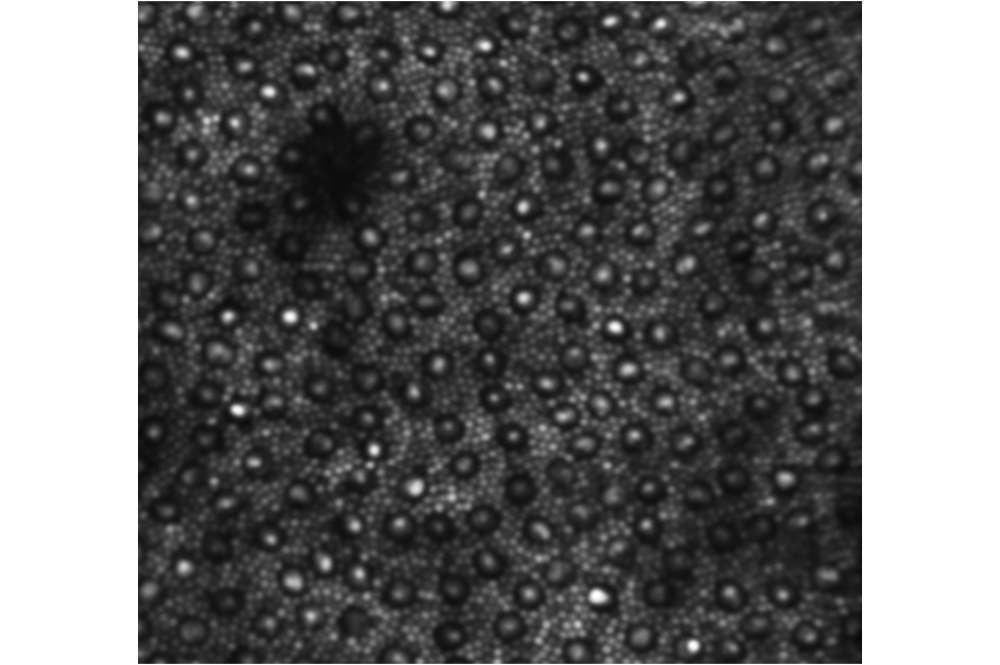

Cystoid Macular Edema in Retinitis Pigmentosa

The bubbled appearance of the top image (AOSLO montage of the photoreceptor mosaic) is caused by the presence of numerous cystic structures in the inner retina (seen in the lower OCT image).